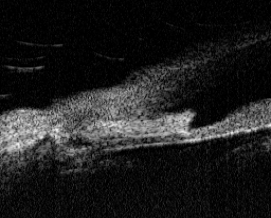

В 11 наших наблюдениях УБМ была единственным

методом, который дал возможность уточнить тип глаукомы, поскольку из-за

помутнений и отека роговицы гониоскопия была невыполнима. УБМ переднего отрезка

глаза этих больных демонстрирует выраженные анатомические изменения УПК,

которые ставят под сомнение успех микрохирургического вмешательства на таких

глазах. В качестве примера приводим УБМ правого глаза больной Л. 86 лет с

закрытоугольной дважды оперированной терминальной глаукомой (СТЭ с базальной

иридэктомией и двухточечная иридоциклоретракция).

На рис. 6 отчетливо видна склеральная ножка в

УПК, истончение корня радужной оболочки, плоская фильтрационная подушечка в

зоне операций. Склеральная шпора не дифференцируется, определить величину УПК,

дистанцию открытия угла, трабекуло-цилиарную и иридо-цилиарную дистанции

невозможно.

Выполнение еще одной фистулизирующей

антиглаукомной операции на слепом болезненном глазу со стойко

декомпенсированным ВГД (42 мм. рт. ст.) и столь выраженными анатомическими

изменениями переднего отрезка было чревато возникновением серьезных осложнений

в ходе операции, а успех ее вызывал сомнения. На энуклеацию слепого

болезненного глаза женщина была категорически не согласна. Произведена

транссклеральная лазерная ЦФК в 1,5 мм. от лимба. Удалось достичь снижения

офтальмотонуса до 27 мм. рт. ст. уже на следующий день после ЦФК, спустя 3

месяца ВГД было 21 мм. рт. ст., через 12 месяцев - 24 мм. рт. ст. Боли в глазу

прекратились, удалось сохранить глаз как орган, больная была удовлетворена

результатом операции.

Рис. 6 - УБМ глаза больной Л. Состояние после

операции СТЭ с иридоциклоретракцией